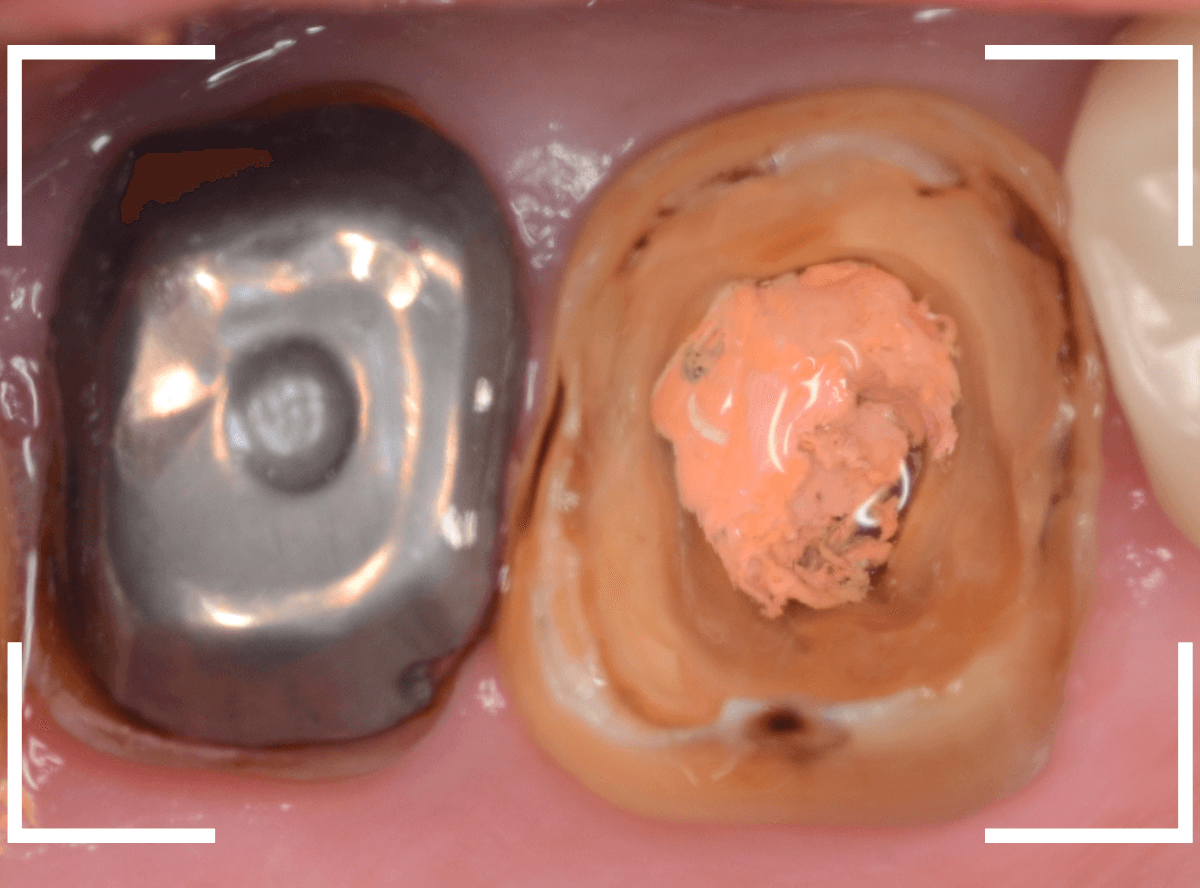

まずは右側のレジンコアから除去します。

ある程度、虫歯とレジンを除去したところです。

幸い、虫歯はあまり深くなさそうですが、歯の根にささったピンの部分が思いの他硬くて、なかなか外れません。

この感じですと、ピンを無理に外さずに土台を作り直しても支障なさそうですが、ここまできたらしっかり中を綺麗にできたらとも思います。

時間がかかりますが、超音波でピンを少しずつ揺らして除去してみます。

かなり時間がかかりましたが、なんとは無事に歯を傷つける事なく、ピンを外すことが出来ました。

綺麗になり、スッキリしましたね。

次は左側のメタルコアを除去します。